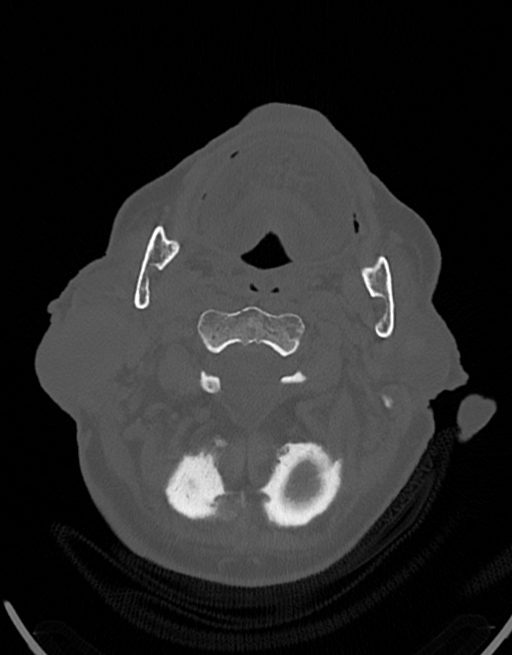

در سی تی اسکن ادنوم پاروتید، دستگاه تصاویری عرضی مقطع ایی از گوش در ناحیه سر و صروت ایجاد می کند. این تصویربرداری از اشعه ایکس برای ایجاد تصویر استفاده می کند.

در سي تي اسکن اسپيرال نازو فارنکس با و بدون کنتراست (مولتي ديدکتور 16 با مقاطع ظريف و بازسازي هاي ساژيتال و کرونال):

– توده نسج نرمي به ابعاد mm 40 x 45 x 60 در ناحيه پاروتيد راست، با enhancement هتروژن پس از تزريق کنتراست مشهود است که مطرح کننده آدنوم پاروتيد مي باشد.

– شواهدي از تهاجم توده به استخوان و عروق اطراف مشهود نيست .

– کلسيفيکاسيون در ديواره شريان هاي کاروتيد دو طرف مشهود است .